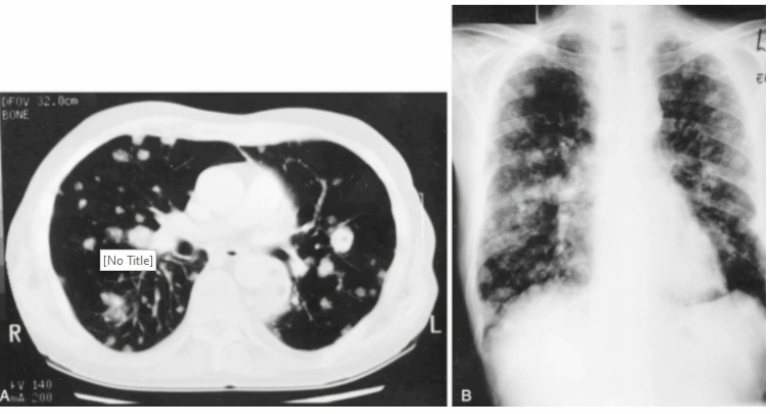

Nocardia - Branching gram positive rod (aerobic)